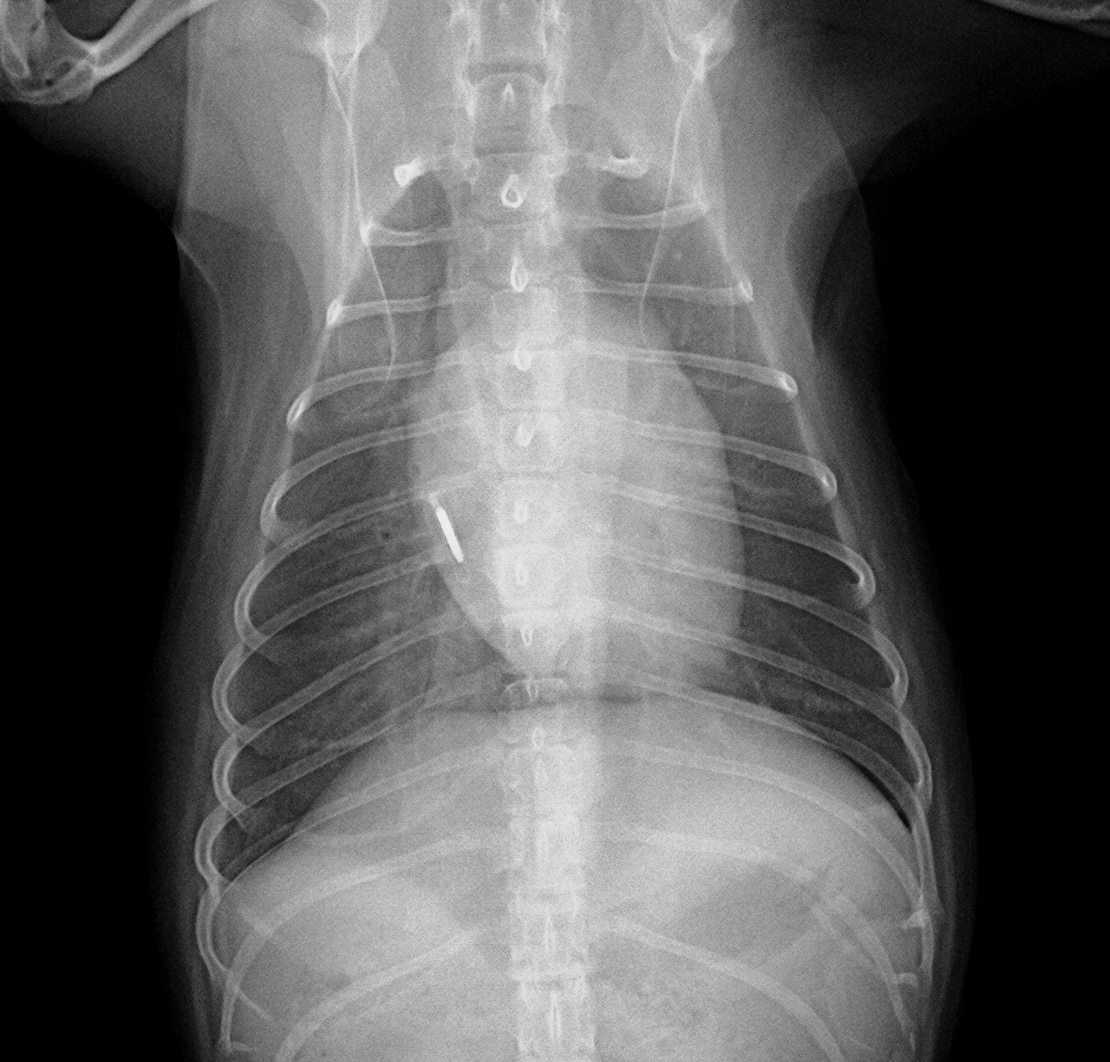

→さらに進行し心不全の症状として肺水腫を発症した段階です。心不全(肺のうっ血)により肺に水が溜まり呼吸困難を呈した状態となっていて、ステージB2よりさらに複数の薬剤での治療が必要不可欠となります。

画像は前述の写真と同じ子の別時期のものです。肺に水がたまり(肺水腫)肺が白く写っています。息苦しさに気づき来院されました。